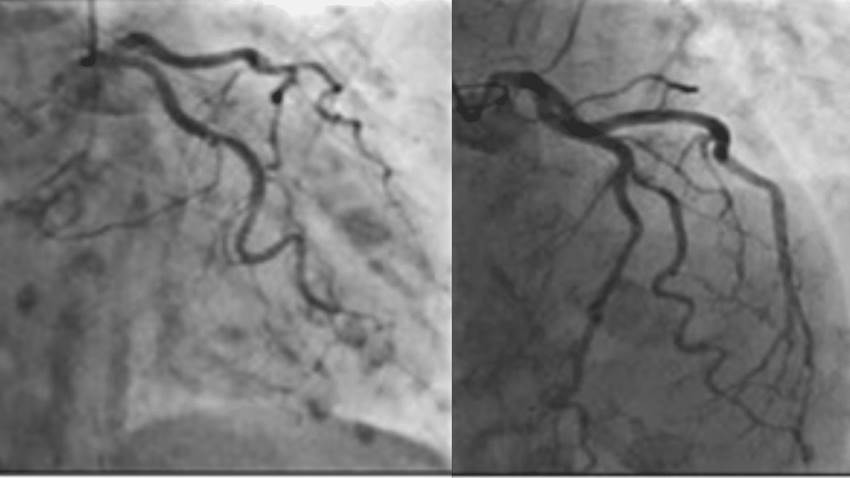

Miocardiopatía de Takotsubo amenazaría la vida adultos mayores que necesiten intervenciones quirúrgicas

Aunque en el campo científico las enfermedades pueden variar en su manifestación y síntomas según vayan resurgiendo los estudios científicos en distin...